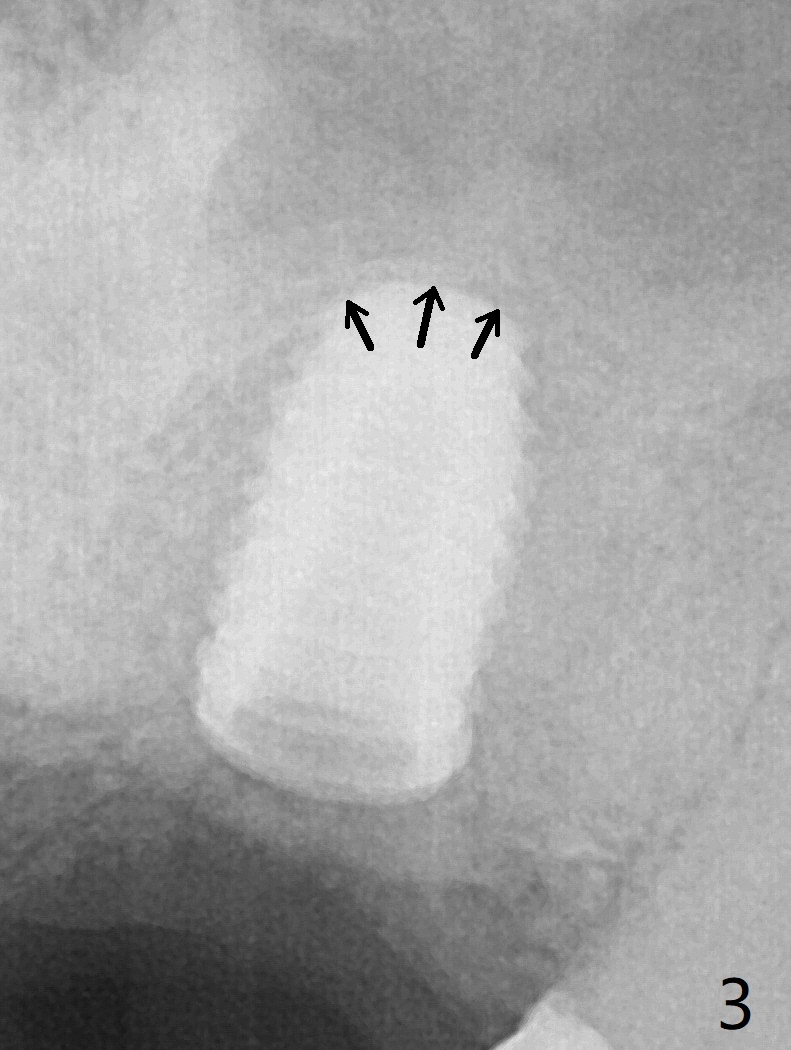

Due to low bone density post large implant (7 mm in diameter) removal with bone graft at #15, osteotomy with guide is underprep (last drill: 3.5x10 vs. 4.5x10 mm (design)). When a 4.5x10 mm dummy implant is placed at the beginning of the 1st line (10.5 mm offset), the torque is ~ 15 Ncm. As a 5x8.5 mm final implant is being placed, the torque increases to 30 Ncm (Fig.1,2) with apparently incidental sinus lift (Fig.3 arrows). The implant remains in place with a healing abutment 2 months 9 days postop (Fig.4). Healing abutment is changed from 5.5x6 to 6.8x5 mm 4.5 months postop when #16 MO composite is redo. There is bone loss at #14 mesially (Fig.5 *) with microthread exposure (<) less than 7 months before loosening.